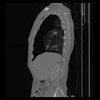

30 CUERPO,CE,Sagittal,3.000,CUERPO,Sagittal,